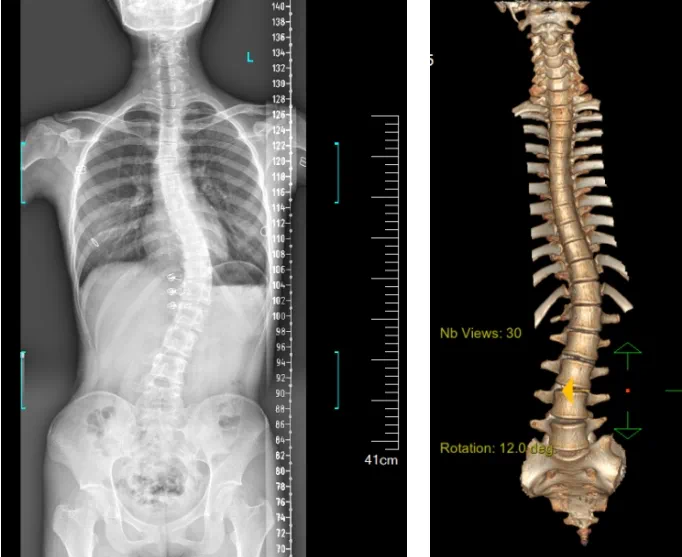

»¼ÕßΪһÃû16ËêÅ®º¢£¬£¬£¬£¬£¬£¬£¬·¢Ã÷¼¹Öù²àÍä1Ä꣬£¬£¬£¬£¬£¬£¬µ½ÄÏ·½Ò½Ôº¸ÓÖÝÒ½Ôº¼¹ÖùÍâ¿ÆÇóÕï¡£¡£¡£¡£¡£¡£¡£¾²éÌ壬£¬£¬£¬£¬£¬£¬»¼Õß×óÓÒÐØÀª²î³Ø³Æ£¬£¬£¬£¬£¬£¬£¬Ë«¼çµÈ¸ß£¬£¬£¬£¬£¬£¬£¬×ó¼çëιÇ¡Æð£¬£¬£¬£¬£¬£¬£¬±³²à³Ê¡°Ìêµ¶±³¡±»ûÐΣ¬£¬£¬£¬£¬£¬£¬ÐØÑü¶Î¼¬Í»Æ«ÀëÕýÖÐÏߣ¬£¬£¬£¬£¬£¬£¬ÐØÑü¶Î¼¹Öù×ó²à͹»ûÐΣ»£»£»£»£»£»¸÷¼¬Í»ÎÞѹʹ¼°ßµ»÷Í´£¬£¬£¬£¬£¬£¬£¬ÓÒ²àÑü²¿°¼ÏÝ£¬£¬£¬£¬£¬£¬£¬Ðظ¹¼°Ñü±³²¿¸ÐÊÜÕý³£¡£¡£¡£¡£¡£¡£¡£¼ì²é·¢Ã÷»¼ÕßÌØ·¢ÐÔ¼¹Öù²àÍ䣬£¬£¬£¬£¬£¬£¬Lenke5CÐÍ£¬£¬£¬£¬£¬£¬£¬Ö÷ÐØÍä51¡ã¡£¡£¡£¡£¡£¡£¡£»£»£»£»£»£»¼Õß¼°¾ìÊô¶ÔÍâ¹Û²»Öª×㣬£¬£¬£¬£¬£¬£¬Îª¸ÄÉÆÍâ¹Û¼°¹¦Ð§£¬£¬£¬£¬£¬£¬£¬ÒªÇóÊÖÊõ½ÃÐÎÖÎÁÆ¡£¡£¡£¡£¡£¡£¡£

¼¹Öù²àÍäÊÇÖ¸¼¹Öù·ºÆð´óÓÚ10¶ÈµÄCÐÍ»òSÐ͵ķÇÕý³£ÍäÇú¡£¡£¡£¡£¡£¡£¡£ÇàÉÙÄêÌØ·¢ÐÔ¼¹Öù²àÍ䣨AIS£©ÊÇÏÖÔÚ×î³£¼ûµÄ¼¹Öù²àÍäÀàÐÍ£¬£¬£¬£¬£¬£¬£¬¶à¼ûÓÚ10ËêÖÁ¹Ç÷À·¢Óý³ÉÊìµÄ¶ùͯºÍÇàÉÙÄ꣬£¬£¬£¬£¬£¬£¬·¢²¡ÂÊΪ2%-4%£¬£¬£¬£¬£¬£¬£¬Å®º¢·¢²¡ÂÊÏÔןßÓÚÄк¢¡£¡£¡£¡£¡£¡£¡£ ¼¹Öù²àÍäµÄΣº¦ÓУº1.Íâ¹Û±äÐΣ¬£¬£¬£¬£¬£¬£¬µ±»¼Õߵļ¹Öù·ºÆðÏÔ×Å»ûÐÎʱ£¬£¬£¬£¬£¬£¬£¬¿ÉÄÜ»áÓ°Ïìµ½Íâ¹ÛÌåÐÍ£¬£¬£¬£¬£¬£¬£¬·ºÆðÆé᫼硢Ìêµ¶±³¡¢¹ÇÅèÇãб¡¢ÊÇ·ÇÍȵÈÖ¢×´£»£»£»£»£»£»2.Ó°Ïì·¢Óý£¬£¬£¬£¬£¬£¬£¬ÈôÊÇ»¼Õߵļ¹Öù²àÍä½ÏÁ¿ÑÏÖØ£¬£¬£¬£¬£¬£¬£¬¼¹ÖùÍäÇúÏÔ×Å£¬£¬£¬£¬£¬£¬£¬ºÜ¿ÉÄÜ»áÓ°Ïìµ½º¢×ÓµÄÕý³£Éí¸ß·¢Óý£»£»£»£»£»£»3.¼·Ñ¹ÐķΣ¬£¬£¬£¬£¬£¬£¬ÓÉÓÚ¼¹Öù²àÍ䱬·¢ÔÚÐØÑü¶Î¾Ó¶à£¬£¬£¬£¬£¬£¬£¬ÍäÇúÑÏÖØÕ߻ᵼÖÂÐØÀªÐýת»ûÐκÍÐØÀªÈÝ»ýϽµ£¬£¬£¬£¬£¬£¬£¬Ó°ÏìÐķη¢Óý¶ø·ºÆðÔ˶¯ÄÍÁ¦Ï½µ¡¢ÐĻůø´ÙµÈÖ¢×´£»£»£»£»£»£»4.Éñ¾ÊÜË𣬣¬£¬£¬£¬£¬£¬Ëæ×ż¹Öù²àÍäµÄ¼ÓÖØ£¬£¬£¬£¬£¬£¬£¬¿ÉÄÜ»áÒýÆð×µ¹ÜÏÁÕ£¬£¬£¬£¬£¬£¬£¬ÉõÖÁ×µ¼ä¿×ÏÁÕ£¬£¬£¬£¬£¬£¬£¬µ±Éñ¾¸ùÁè¼Ý×µ¼ä¿×Ïà¹ØÎ»ÖÃʱ£¬£¬£¬£¬£¬£¬£¬¿ÉÄÜ»áÔì³ÉÉñ¾Õ¥È¡ÉõÖÁ̱»¾¡£¡£¡£¡£¡£¡£¡£